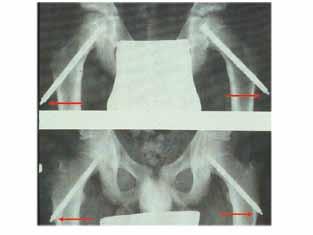

50 årig man som två år tidigare opererats

med en ocementerad protes. Han blev aldrig smärtfri efter operationen. Söker på grund av lårsmärtor som förvärras vid belastning. Daglig hög analgetikakonsumtion. CRP 7 (normalvärde <5). Använder 1 kryckkäpp.

a. Vilken diagnos bör du misstänka i första hand? (1p)

b. Motivera ditt svar och ange förslag till behandling. (2p)

a. Patienten har smärtor både i vila och vid belastning. CRP är antytt förhöjd. Protesen har en bred zon proximalt. Det föreligger en breddökad kortex och uttalade periostala pålagringar.

Mycket talar för en djup och lågvirulent infektion. (1 p). (Stammen är sannolikt lös även om man inte kan se någon säker sjunkning. Cupen sitter troligen fast eftersom man inte ser någon zon)

b. Man bör göra en ledpunktion och odla helst vid två efterföljande tillfällen (1p). Härefter protesbyte (1p). Om agens inte är känt bör revision utföras i två seanser.